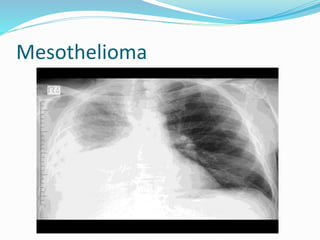

‫ورم‬

‫الريقة‬

‫المتوسطة‬

Mesothelioma

‫الجنبي‬

‫أو‬

‫البريتواني‬

 ‫الخاصة‬ ‫المضاعفات‬ ‫أهم‬ ‫باألميانت‬ :  ‫الرئة‬‫انتفاخ‬  ‫المزمن‬ ‫القصبات‬ ‫التهاب‬  ‫الرئة‬ ‫سرطان‬  ‫ورم‬ ‫الريقة‬ ‫المتوسطة‬ Mesothelioma ‫الجنبي‬ ‫أو‬ ‫البريتواني‬